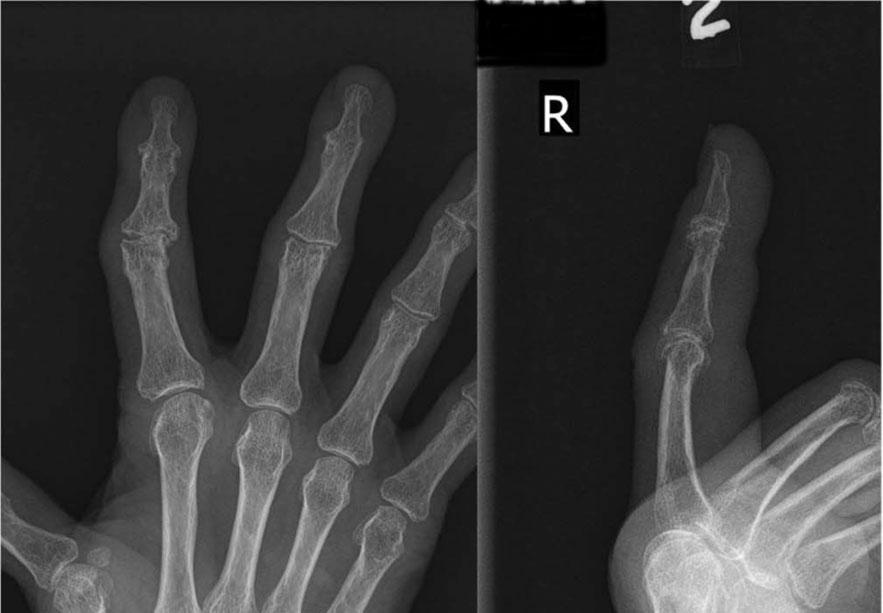

X-ray Showing Finger Arthritis and Finger Joint Replacement

(Left) X-ray of a patient with arthritis throughout the hand, particularly affecting the MCP joints. (Right) X-ray of the patient after replacement of the index through little finger MCP joints with pyrocarbon implants.

Reproduced from Carlson Strother C, Moran S, Rizzo M. Small Joint Arthroplasty of the Hand: An Update on Indications, Outcomes, and Complications. J Am Acad Orthop Surg 2023;31:793-801.